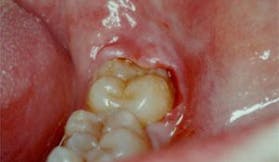

L'indicazione più frequente all'estrazione dei denti del giudizio è l'assenza di spazio nella mandibola e/o mascella necessaria ad una corretta eruzione. Altre indicazioni sono l'eruzione di questi con angolazioni anomale o che possono danneggiare i denti vicini.

I denti del giudizio possono anche causare problemi di infiammazione ai tessuti parodontali a causa di un'incompleta eruzione che spesso per ristagno batterico può portare ad una infezione cronica della gengiva circostante il dente.